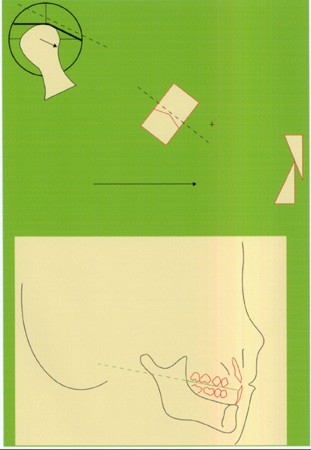

Primera Parte RESUMEN: La alta complejidad inherente a los procedimientos de Rehabilitación Oral, obligan al profesional que la ejerce a basarse en parámetros multidisciplinarios, a veces lo suficientemente intrincados que hacen imposible la práctica de la misma, sin la presencia en su mente de una clara concepción de la Oclusión. The extreme complexity of Oral Procedures, make it imperative for the working professional to rest on multidisciplinary parameters, sometimes so complex that make impossible its practice without the presence of a clear idea of Oclusion. DESARROLLO Suele ser sumamente árido el abordaje de un tema como Oclusión, desde la perspectiva de nuestro diario trabajo ,con todo el strees que este conlleva, con toda la lucha que significan citas, honorarios, diferentes personalidades de los pacientes, inquietudes de los mismos, etc. «LA MEJOR OCLUSIÓN ES LA QUE TIENE LA MEJOR DESOCLUSIÓN» Básicamente, podemos como desde hace ya muchos años se viene haciendo; clasificarlos en: A)Determinantes Posteriores (fijos) Más contemporáneamente, en: I-Mecanismos Primarios: A.T.M. GUIA ANTERIOR INCLINACIÓN DEL PLANO OCLUSAL CURVA SAGITAL DE SPEE FORMA DE LA ARCADA III-Mecanismos Elementales CRESTAS TRIANGULARES INTERNAS Analicemos cada uno de ellos: Es evidente, que la reproducción de las características de la A.T.M., en nuestro aliado fundamental, el Articulador; es imprescindible. Partiendo de la premisa de obtener una OCLUSIÓN MUTUAMENTE PROTEGIDA, para luego arribar al concepto de OCLUSIÓN MUTUAMENTE COMPARTIDA, concepto este que desarrollaremos durante el transcurso de las distintas entregas, analizaremos cada uno de los FACTORES DETERMINANTES DE LA OCLUSIÓN. El primero de ellos, por ser fijo e invariable, solo diremos que: son sus INCLINACIONES PLANARES, o sea : A-INCLINACIÓN DE LA TRAYECTORIA CONDILEA C-BENNET INMEDIATO articuladores totalmente ajustables) D-DISTANCIA INTERCONDILAR. En cuanto a la GUÍA ANTERIOR, mecanismo primario y por supuesto anterior, provee al cuerpo mandibular; del camino a recorrer durante las excursiones protrusivas y lateralidades, a través del vínculo entre las piezas dentarias anteriores, superiores e inferiores. En un corte sagital, podemos observar la relación entre estos donde vemos que se vinculan sin entrar en un contacto franco, sino más bien en una relación de vencindad muy intima a la que llamamos: PUNTO DE ACOPLAMIENTO. Otros factores fundamentales de la GUÍA ANTERIOR son : A-ALTURA FUNCIONAL B-PUNTO DE ACOPLAMIENTO En cuanto a los SURCOS, sabemos que durante una Transtrusión, las cúspides fundamentales generan surcos sobre las piezas que antagonizan. Dichos surcos proveen de una vía de escape a las cúspides antagonistas para evitar colisiones, con las indeseables fuerzas laterales cuya gravedad ya conocemos. MECANISMOS SECUNDARIOS La CURVA FRONTAL DE WILSON, se observa invertida a nivel de los caninos y de los primeros premolares. El PLANO OCLUSAL, en realidad no es ningún plano, sino la sumatoria de muchos MICROPLANOS, los cuales individualmente pueden constituir factores presentes en la OCLUSIÓN, pero auténticos problemas para la DISCLUSIÓN. La CURVA SAGITAL DE SPEE, denominada originariamente de BALKWIL-SPEE, fue concebida como una curva. El cuarto factor SECUNDARIO: el ANCHO DE LA ARCADA, es evidente que variando los ejes de rotación , alrededor de las diferentes distancias ;cambiará la dirección de los escapes (surcos), de los elementos que en el se muevan (cúspides). MECANISMOS ELEMENTALES Los CUATRO NIVELES DE OCLUSIÓN y las CRESTAS TRIANGULARES INTERNAS, constituyen de por si, la herramienta ejecutora de las funciones gnáticas. A- ELEVACIONES 1-Puntas Cuspídeas B-DEPRESIONES 1-Fosas SURCOS DE DESARROLLO De las CRESTAS TRIANGULARES INTERNAS, acentuamos su importancia en ellas dado que son las efectoras finales de la molienda, y su triangularidad debe tener su base partiendo del surco y su vértice terminando en la Punta Cuspídea, condición importante para evitar colisiones durante la transtrusión (movimiento de lateralidad ). EFECTOS DE LA VARIABILIDAD DE LOS FACTORES DETERMINANTES DE LA OCLUSÍON Cada uno de los determinantes influye aumentando o disminuyendo tanto la DESOCLUSIÓN como la ALTURA CUSPÍDEA INCLINACIÓN DE LA TRAYECTORIA SAGITAL INCLINACIÓN DEL PLANO OCLUSAL RADIO DE CURVATURA DE LA ÁNGULO DE LA TRAYECTORIA ALTURA DEL PUNTO DE LATERO SURTRUSIÓN / MOV. DE BENNET INMEDIATO CURVA FRONTAL DE WILSON SURCOS BIBLIOGRAFÍA Dibujos y esquemas tomados del libro: Oclusión Orgánica…un camino hacia la Rehabilitación Oral. 1)William Mc Horris,B.S.,D.D.S. Oclusión. Con especial énfasis sobre :El rol funcional y parafuncional de los dientes anteriores. 2)Von Spee , Craff(Anatomista alemán, describió la curva de compensación de la articulación de molares y premolares).CURVA DE SPEE 1.89 3)Stuart,D.»Some aspects of the inervation teeth.»Procedings of Royal Society of Medicine.20:1675,19274)Muhleman,H. y Savdir,S»Tooth movility-its causes and significance»Journal of Periodontology ,36:153,Marzo ,Abril,1965. 4)Muhleman,H. Y Savdir,S»Toothmovility its causes and significance» Journal of Periodontology,36:153,marzo,abril,1965. 5-Oclusión y Diagnóstico en Rehabilitación Oral. 6-Anatomia Odontológica. -A contribution to the study of the movementes of the mandible. 8-Celenza F.W, Nadeskin J.F.,Oclusión.Situación actual. 9-D´Amico 10-Dawson P.E. 11-Huffman -Regenos. 12-Hobo S.-Takayama H.A. 13-Lucia V.O 14-Mc Horris. 15-Mc Horris. 13-Posselt U. 16-Stuart C. 17-Vartan Veshnilian

Múltiples son los factores que influyen sobre la morfología y función de las caras oclusales. Los hay de importancia absoluta y determinativa, y algunos ;cuya influencia es más relativa.

Podemos decir que los factores que determinan la Oclusión, son precisamente aquellos que producen DESOCLUSIÓN.

Ahora bien, como; la variabilidad de cada uno de estos factores influye sobre nuestros patrones oclusales, es una cuestión a desmenuzar:

A mayor inclinación , mayor altura cuspídea, mayor desoclusión.

A mayor inclinación ,menor altura cuspídea, menor desoclusión.